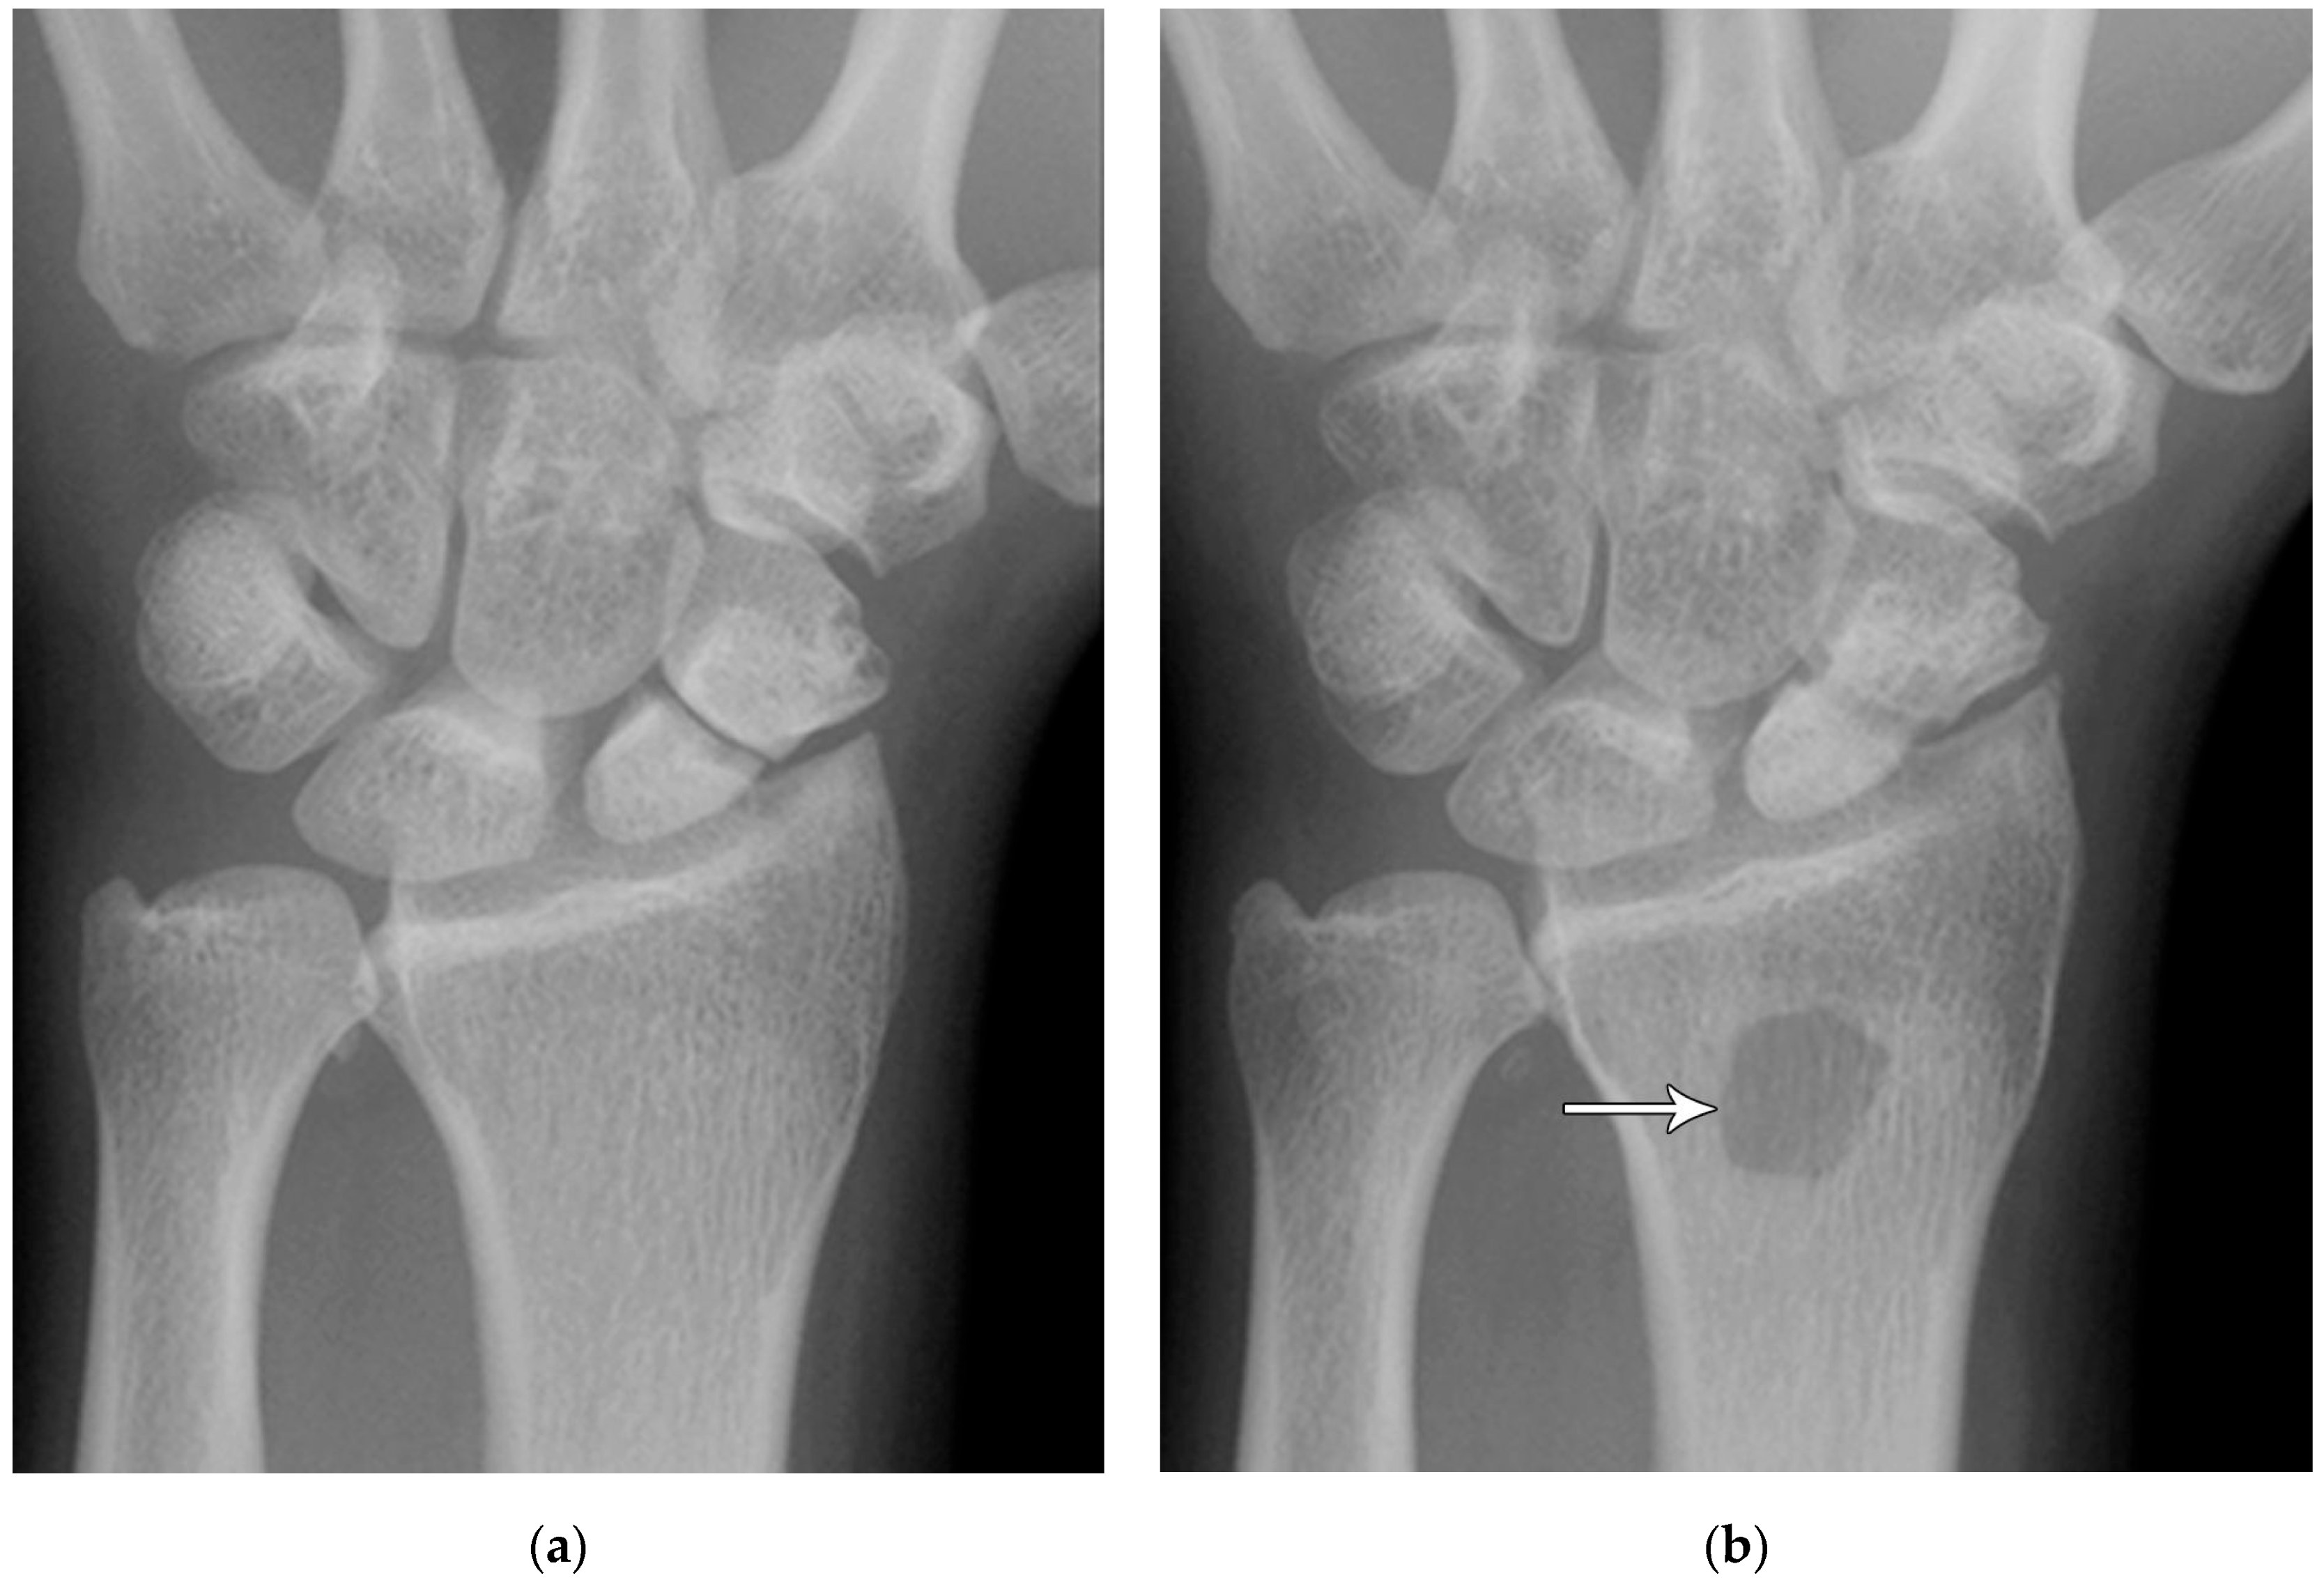

Figure 5. (a) PA radiograph showing marked sclerosis (arrow) of the proximal pole of the scaphoid after a scaphoid fracture. (b) Coronal reformatted CT in a different patient showing sclerosis (arrow) of the proximal pole of the scaphoid after a scaphoid fracture, indicating osteonecrosis.

Common scaphoid fracture complications include avascular necrosis and nonunion [10]. Avascular necrosis is a dreaded outcome resulting from the loss of the proximal arterial supply due to the distal entry point of nutrient vessels. This retrograde perfusion of the proximal pole makes it vulnerable to losing its vascular supply when fractured. Sclerosis of the proximal pole indicates osteonecrosis (Figure 5). With scaphoid nonunion, biomechanical alterations contribute to rapidly progressive degenerative arthritis and instability referred to as scaphoid nonunion advanced collapse (SNAC) [16]. Nonunion occurs in 5–10% of cases and has a higher incidence in displaced fractures (Figure 6). During wrist extension, the distal scaphoid fragment rotates into flexion while the proximal scaphoid fragment extends with the lunate. The resultant abnormal contact between the distal fragment and radius begins the first stage of degenerative collapse. This progresses into the second stage as scaphocapitate osteoarthritis develops and finally to the third stage with progression to capitolunate osteoarthritis and proximal radial migration of the capitate dorsal to the lunate. Treatment of SNAC wrists, depending on the degree and severity of the osteoarthritic collapse, includes scaphoidectomy with four-corner arthrodesis or wrist fusion [17]. Four-corner fusion helps reduce joint pain while maintaining some range of motion, as opposed to total wrist fusion (Figure 7). Another option is proximal row carpectomy with resurfacing capitate pyrocarbon implant placement [18].